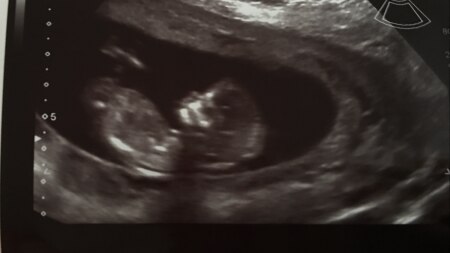

Hallo Mädels. Mein Tag war so voll, deshalb kann ich erst jetzt schreiben. Bei dem Mäuschen war alles super. Die Werte sind alle top und es gibt nichts auffälliges. 72g und fast 7 cm. So groß ist es schon. Und heute wurde immer wieder am Daumen oder am Zeh gelutscht Gerade war ich beim preKanga. Ganz schön anstrengend, aber es hat Spaß gemacht. Schlaft gut und danke fürs Daumen drücken

Tolles Foto und schön, dass dein Termin super war :)